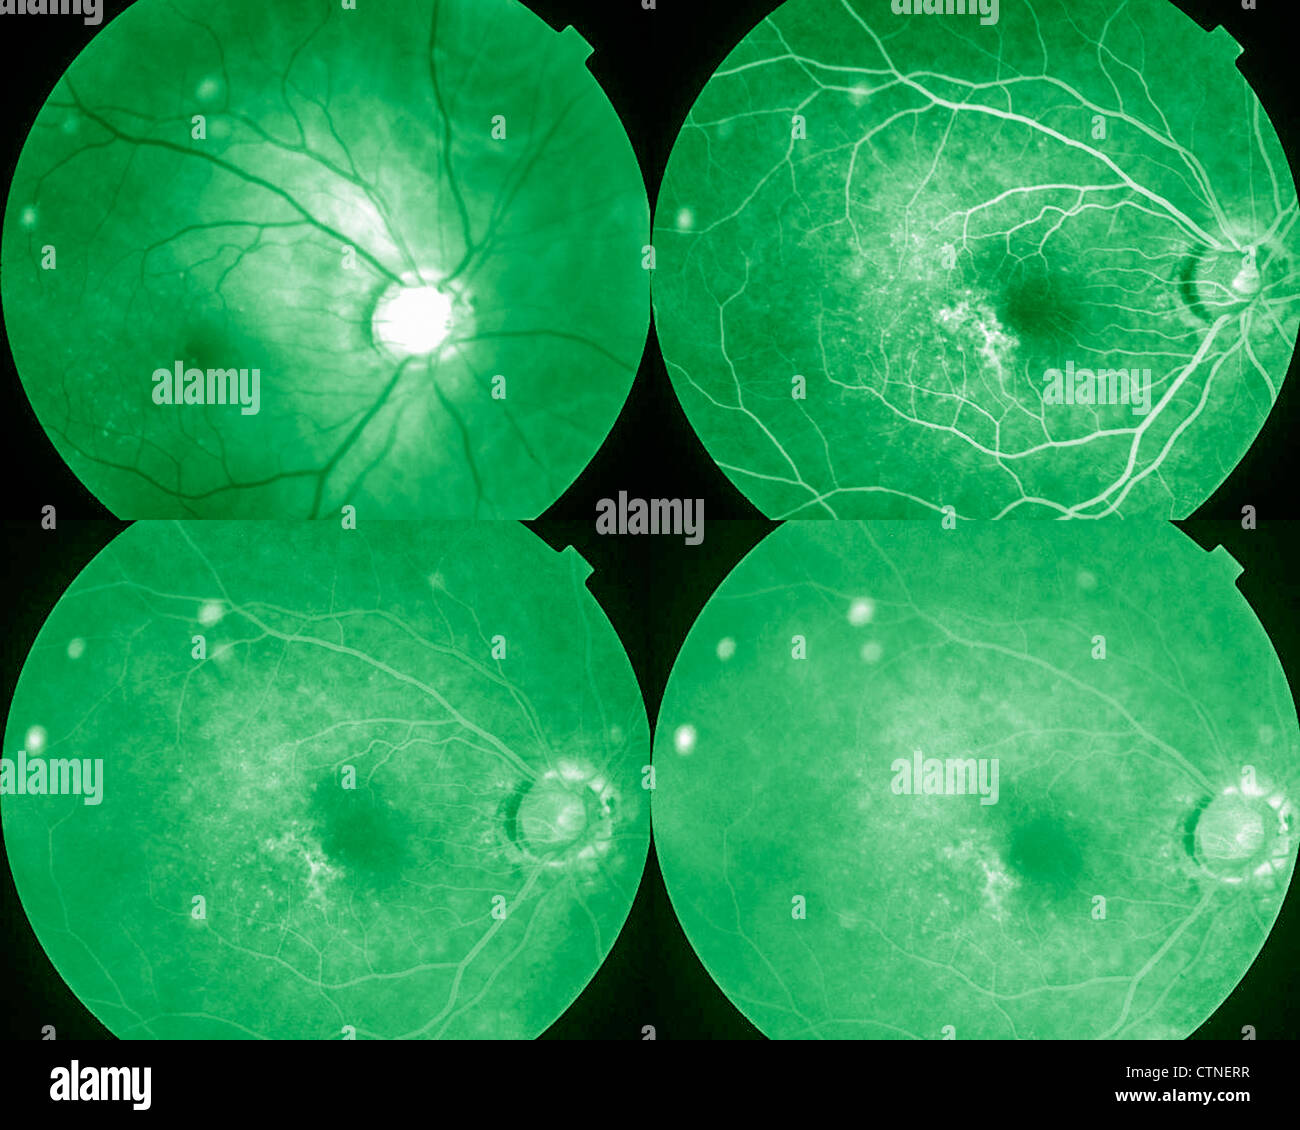

Four phases eye angiogram Stock Photohttps://www.alamy.com/image-license-details/?v=1https://www.alamy.com/stock-photo-four-phases-eye-angiogram-49645115.html

Four phases eye angiogram Stock Photohttps://www.alamy.com/image-license-details/?v=1https://www.alamy.com/stock-photo-four-phases-eye-angiogram-49645115.htmlRMCTNERR–Four phases eye angiogram